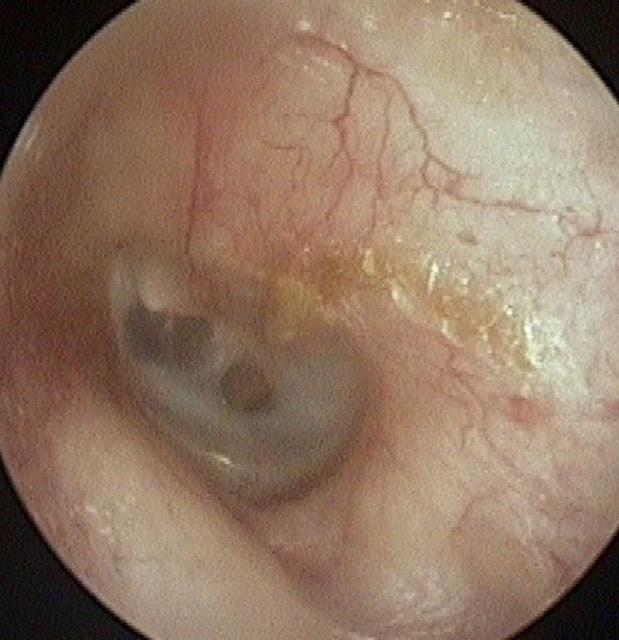

Perforation